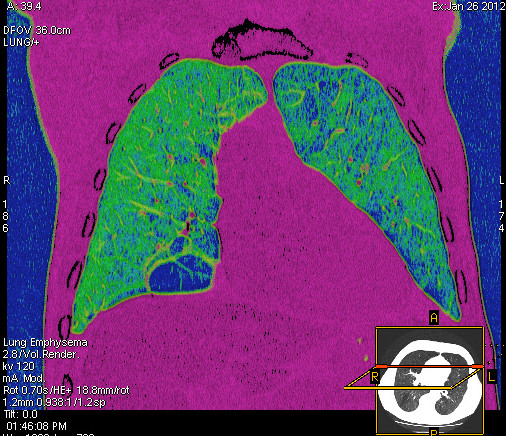

Foto: Aleksandar Ivković Foto: Aleksandar Ivković Foto: Aleksandar Ivković Strašna razlika kod pluća pušača i kovid pozitivne osobe autor: Božica Luković Zdravlje 23. jan. 2021. 12:06 > 23. jan. 2021. 12:15 0 Podeli vest: Radiolog Aleksandar Ivković od početka pandemije daje korisne informacije o svim aspektima kovida 19. On je nedavno uporedio rendgen snimke pluća zdrave osobe, pušača, osobe koja je zaražena gripom H1N1, a onda i osobe koja ima kovid 19. Razlike su zapanjujuće. Podeli vest: Oglas Objavu doktora Ivkovića sa njegovog bloga "Ljudi i ostale laži" prenosimo u celosti."Nedavno sam video u medijima da je neko preneo rdg sliku i razlike kod nalaza zdrave osobe, pušača i bolesnog od kovida 19. Kako nisam baš previše zadovoljan onim što je prikazano, evo kako to izgleda u našoj varijanti. Zdrava osoba CT nalaz kod zdrave osobe podrazumeva da ne postoje nikakvi poremećaji strukture plućnog parenhima, da su krvni sudovi uredni i da nema suženja disajnih puteva, kao i da nema uvećanih limfnih žlezda u hilusima pluća i medijastinumu. Foto: Aleksandar Ivković | Foto: Aleksandar Ivković * Foto: Aleksandar Ivković | Foto: Aleksandar Ivković Zdrava muška osoba mesec dana nakon zapaljenja pluća tokom kovida 19. Nalaz bez nekih posebnih problema iako se naziru tragovi zapaljenja. Snimak u boji je zdrava osoba, nepušač, bez ikakvih bolesti pluća u istoriji. Grip H1N1 Pokazaću samo drastične nalaze kod gripa H1N1, to je znači onaj grip koji je izazvao epidemiju španske groznice i epidemiju 2009. godine koja još uvek nije prestala (svake godine imamo makar 15%). Foto: Aleksandar Ivković | Foto: Aleksandar Ivković * Foto: Aleksandar Ivković | Foto: Aleksandar Ivković * Foto: Aleksandar Ivković | Foto: Aleksandar Ivković * Foto: Aleksandar Ivković | Foto: Aleksandar Ivković Nisu svi pacijenti imali ovakve nalaze, pokazujem one koji su imali tešku kliničku sliku. Kod gripa se sve odvija obično u sedam dana. Kao što se vidi, zapaljenje je bilo jednostrano, uglavnom. Ali kada je dolazilo do pogoršanja, onda je centralno obostrano dolazilo do edema pluća. Pušenje Kod pušača postoje razne varijante nalaza na plućima. U principu nisu tako dramatične kao što su zapaljenja. Nalaz na plućima kod pušača može biti potpuno normalan. Ovo ne pišem zato što podržavam pušenje, naprotiv, veliki sam protivnik, ali iznošenje laži nikada nije dobro. Dve dijagnoze su bitne kao posledica pušenja. Prva je hronična plućna opstruktivna bolest: Foto: Aleksandar Ivković | Foto: Aleksandar Ivković * Foto: Aleksandar Ivković | Foto: Aleksandar Ivković * Foto: Aleksandar Ivković | Foto: Aleksandar Ivković Jasna je razlika u nalazu, posebno na ovim slikama u boji, gde su ta plava polja delovi pluća koji su propali zbog cigareta (može da se uporedi sa zdravim plućima iznad).Druga bolest koja je česta kod pušača je u svakom slučaju karcinom. Foto: Aleksandar Ivković | Foto: Aleksandar Ivković * Foto: Aleksandar Ivković | Foto: Aleksandar Ivković * Foto: Aleksandar Ivković | Foto: Aleksandar Ivković * Foto: Aleksandar Ivković | Foto: Aleksandar Ivković Tkivo koje raste unutar pluća i razjeda ga. Takav je nalaz kod karcinoma pluća. Često je uzrok upotreba cigareta. Kovid 19 O kovidu sam pisao puno puta. Evo nekih slika, radi poređenja. Foto: Aleksandar Ivković | Foto: Aleksandar Ivković * Foto: Aleksandar Ivković | Foto: Aleksandar Ivković * Foto: Aleksandar Ivković | Foto: Aleksandar Ivković * Foto: Aleksandar Ivković | Foto: Aleksandar Ivković Nakon što pacijent bude izlečen od gripa ili kovida 19, pluća se mogu vratiti u normalu.To je razlika u odnosu na posledice upotrebe cigareta. Ovi snimci nisu postavljeni da bi se poredile bolesti, već da bi se ukazalo kako različite bolesti deluju na pluća. I ono što je veoma važno, ako neko dobije jednu od ovih bolesti, ne znači da u toku života neće dobiti drugu.Ne pišem zato smo smatram da sam najpametniji ili najpozvaniji da objašnjavam, nisam kao neki pojedinci ubeđen da samo ja imam znanje i istinu, pišem jer drugi ćute. Pišem jer ima i puno onih koji iznose laži, mora se tome stati na put.A ovi, koji pišu da sam umro, da sam oboleo od karcinoma, ovi koji mi žele da nađem dobro grobno mesto, šta da vam kažem, vi ste mi inspiracija. Svesni ste da sam u pravu i odlično znam da ste već uradili sve da se vakcinišete i mnogi od vas će to uraditi pre mene ali i dalje ćete ubeđivati druge da se ne vakcinišu i da je dobro za njih da se razbole i umru. Ima puno reči za vas u svim našim slovenskim jezicima, znate vi sami šta ste", piše dr Ivković.***Bonus video:https://youtu.be/MWucTT0qBsIPratite nas i na društvenim mrežama:FacebookTwitterInstagram Dr Lukić otkrio spisak svih antibiotika za kovid upalu pluća Zdravlje 0 Dr Žujović: Kako oporaviti pluća posle korone Zdravlje 0 Pet znakova da ti je kovid zahvatio pluća Zdravlje 0 Virusolog Ana Banko ruši veliku zabludu o ruskoj vakcini Emisije 0 aleksandar ivković korona kovid pluća snimak pluća Pratite nas na društvenim mrežama: Koje je tvoje mišljenje o ovoj temi? Učestvuj u diskusiji ili pročitaj komentare Budite prvi koji će ostaviti komentar Pošalji komentar Pročitaj komentare (0)